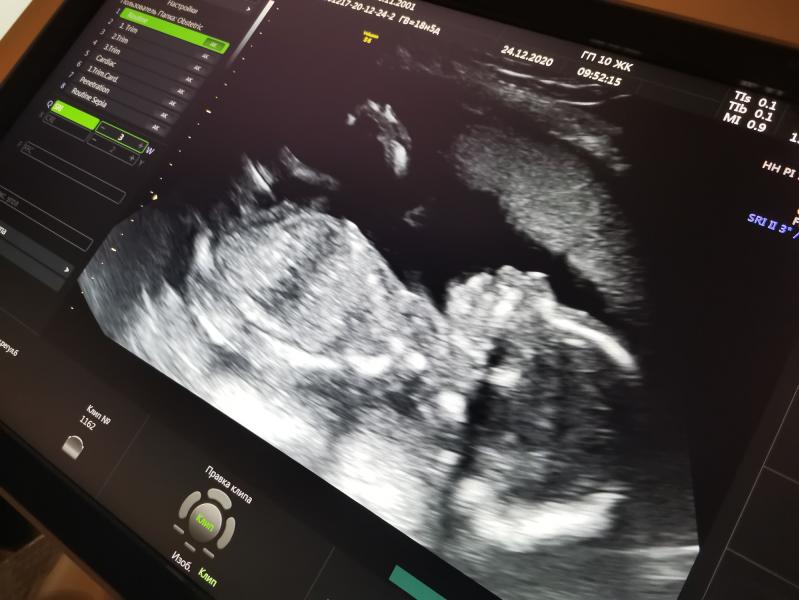

На узи (2 скрининг) были 24 декабря.

Малыш чувствует себя хорошо, все показатели в норме. Вес его ~ 300гр. Нам подтвердили, что Мальчик 100%. ( так как пол, мы ещё узнали на 16 недели) Имя ещё не выбрали.